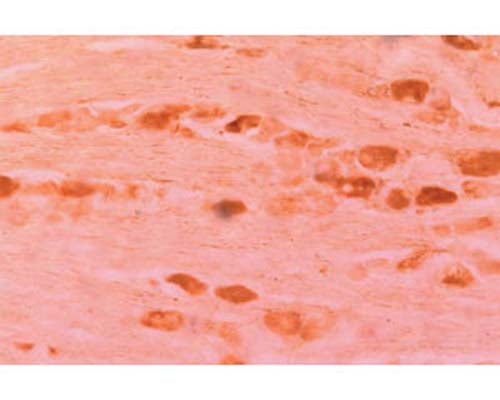

Anti-Neurturin (NTN) Antibody

Our Anti-Neurturin (NTN) rabbit polyclonal primary antibody detects human, mouse, and rat Neurturin (NTN), and is whole serum. It is validated for use in IHC-Frozen.